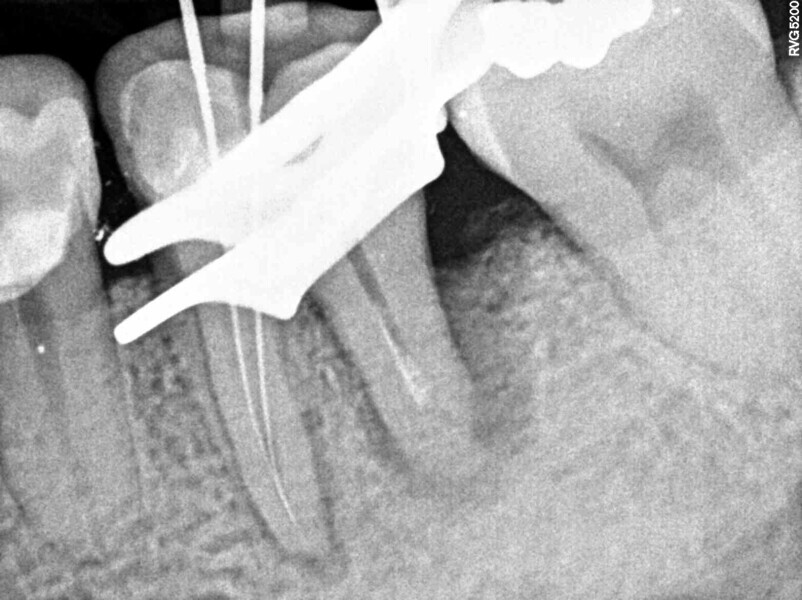

A 50-year-old patient with non-contributory systemic disease presented with the main complaint of pain on mastication. He reported having had a direct restoration on the mandibular left first molar six months earlier. On clinical and radiographic examination, a large, overextended amalgam Class II filling was observed as well as a J-shaped radiolucency on the distal aspect of the tooth (Fig. 1). A buccal swelling oriented distally was also present, as were characteristics of occlusal wear compatible with bruxism on the patient’s dentition. The tooth had pain on percussion and responded negatively to electrical and thermal stimulus tests. When probing in the region of the abscess, a 9 mm isolated pocket was identified (Fig. 2). The tooth was diagnosed with pulpal necrosis and periapical abscess and a suspected VRF. To confirm the presumptive diagnosis, an access cavity was prepared under dental dam isolation and under the dental operating microscope. When the previous restoration was removed, a longitudinal fissure line was detected on the distal aspect of the pulpal floor at higher magnification (10×).

Upon this finding, the hemisection procedure was discussed with the patient, and he gave his full consent to perform it. Initially, the distal canal was gently irrigated with sodium hypochlorite at a 5% concentration and the canal medicated with calcium hydroxide (Fig. 3). At a second appointment 15 days later, the buccal abscess had receded (Fig. 4). The mesial root canal was then treated conventionally, determining the working length with an electronic apex locator (Root ZX II; Morita), performing instrumentation with nickel–titanium files (Pro-Flexi Files, Denco) and obturating with gutta-percha and a bioceramic sealer using the single-cone technique (CeraSeal, Meta Biomed). A resin core was placed with a dual-polymerising composite (CompCore AF, Premier Dental; Figs. 5 & 6).